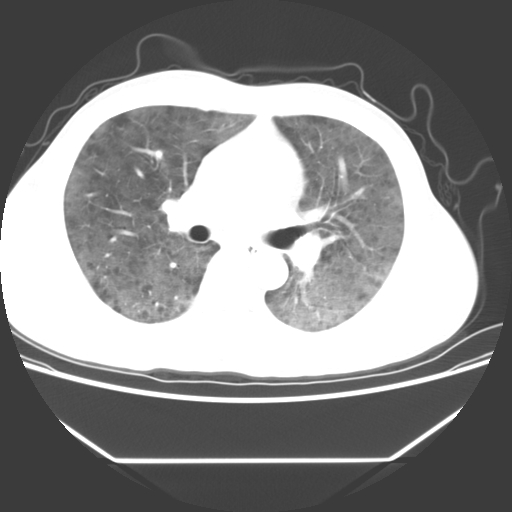

病人55岁,咳嗽,胸闷

忘了传病史了,病人55岁,咳嗽,胸闷

两肺部呈“毛玻璃”状改变,原因待查考虑感染性病变

病人是否发烧,两肺“磨玻璃”影,其间见空气支气管征和碎路石征。考虑肺泡蛋白沉着症。

两肺广泛对称磨玻璃样影,密度不均,考虑机遇性肺部感染。

双肺弥漫磨玻璃样病变,病史很重要。有感冒或发烧史,甲流不除外。无发烧可考虑肺泡蛋白沉积,但肺泡蛋白沉积边缘往往较清晰,与正常肺组织分界清晰

两肺弥漫间质性病变,考虑肺泡蛋白沉着症。建议进一步检查。

两肺“磨玻璃”影,其间见空气支气管征和碎路石征。考虑肺泡蛋白沉着症。

此病人我并没有见到,病史没有得到更详细,但此病人据说有发低热,请教各位老师,此病人像不像卡氏肺囊虫肺炎

考虑pcp?不像肺泡蛋白沉着症。